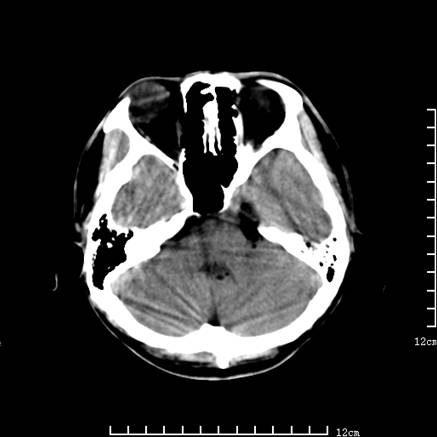

以下是引用jiajie在2008-9-5 22:25:00的发言:[br]男,22岁,头痛1月余。脑室、脑池内病变ct值约-120hu。[br][br]双侧侧脑室内低密度影充填,出现脑脊液脂肪平面,脑池内亦可见弥散分布的斑点状低密度影,脑室脑池未见明显扩大。[br]考虑胆脂瘤破裂后内容物进入脑脊液。